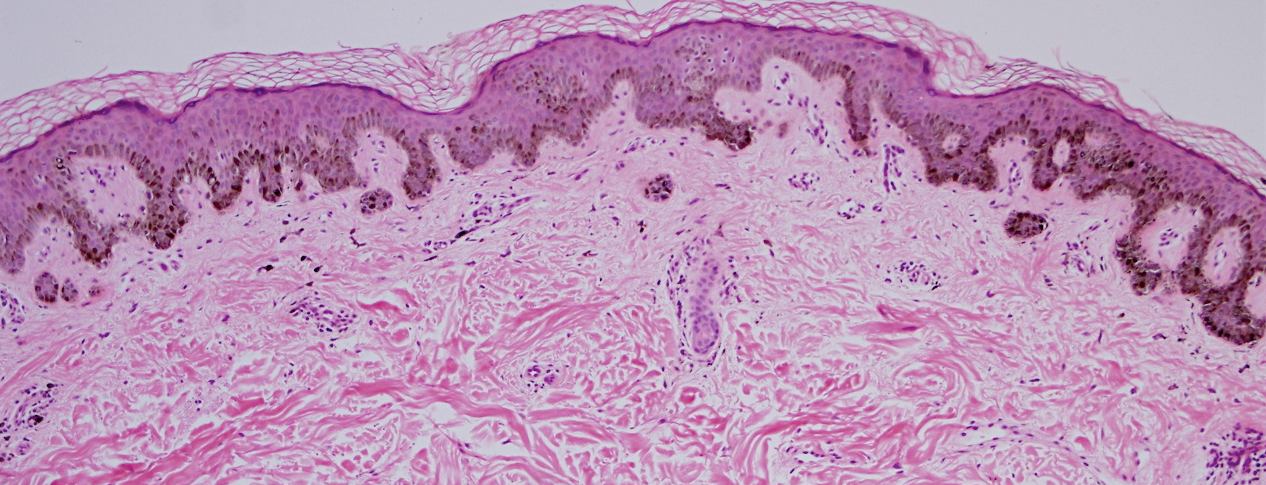

VA121: Left Mandibular Ramus, Junctional Melanocytic Nevus, Dysplastic

- Arrows indicate rete elongations

VA121: Left Mandibular Ramus, Adjacent, Normal